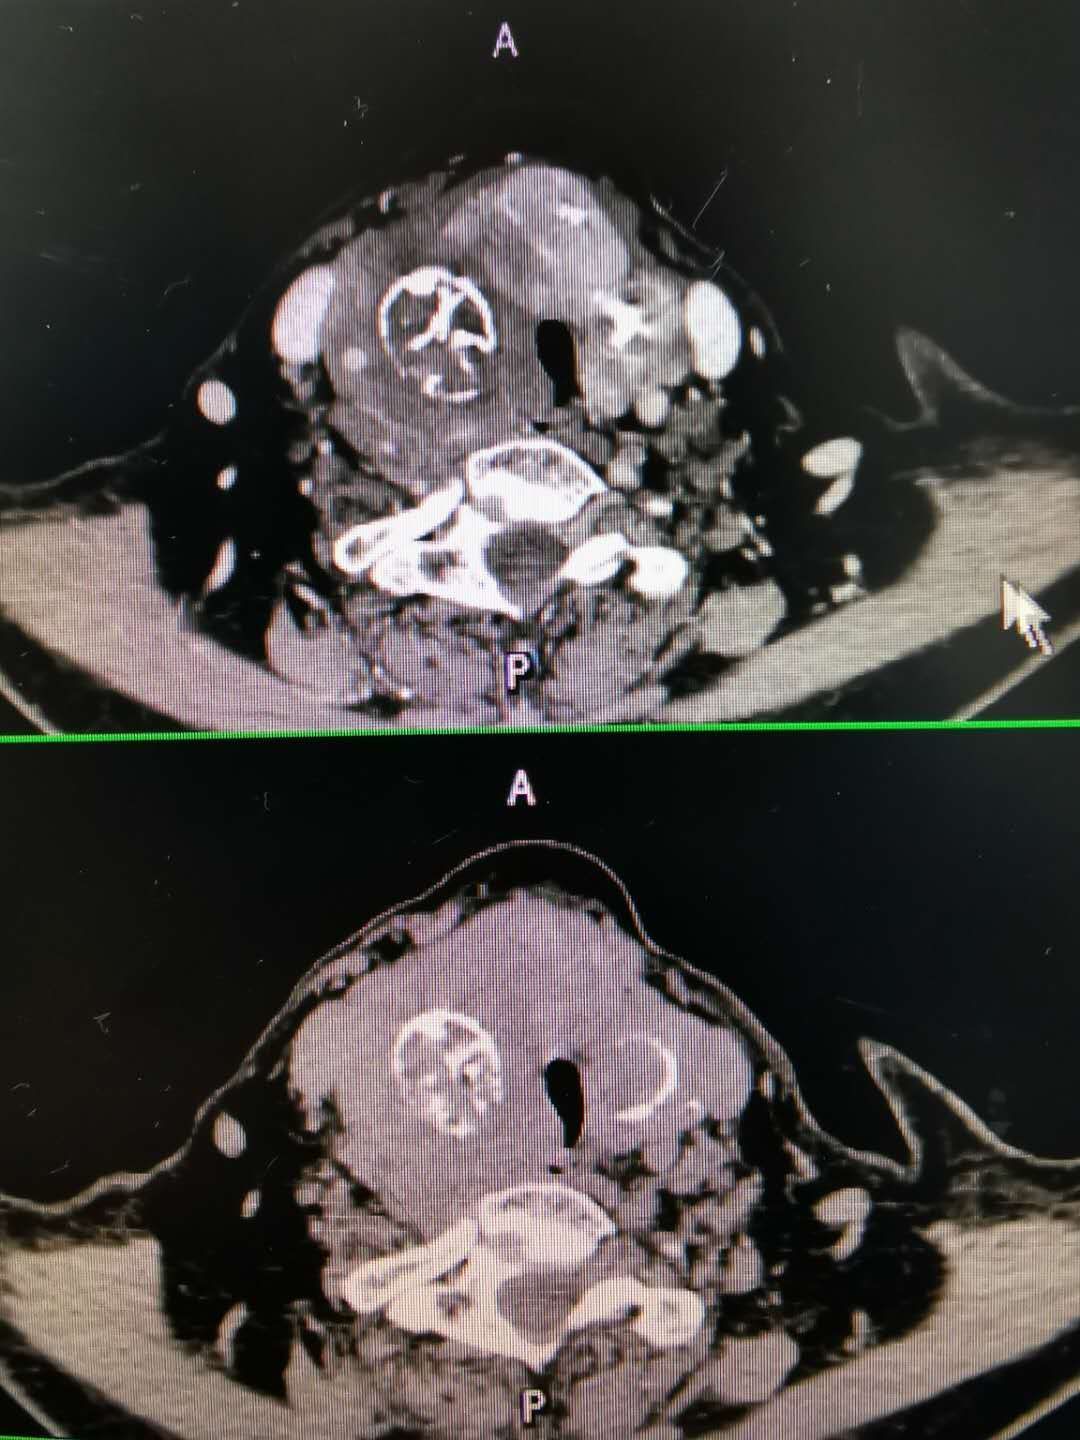

甲状腺良性肿瘤恶变甲状腺未分化癌1例原创